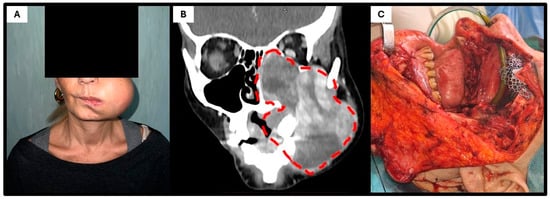

| 54 | Present case | Italy | 54 | F | Left maxilla | No | 10 | No | nCT + S + aRT | 8 (DF) |